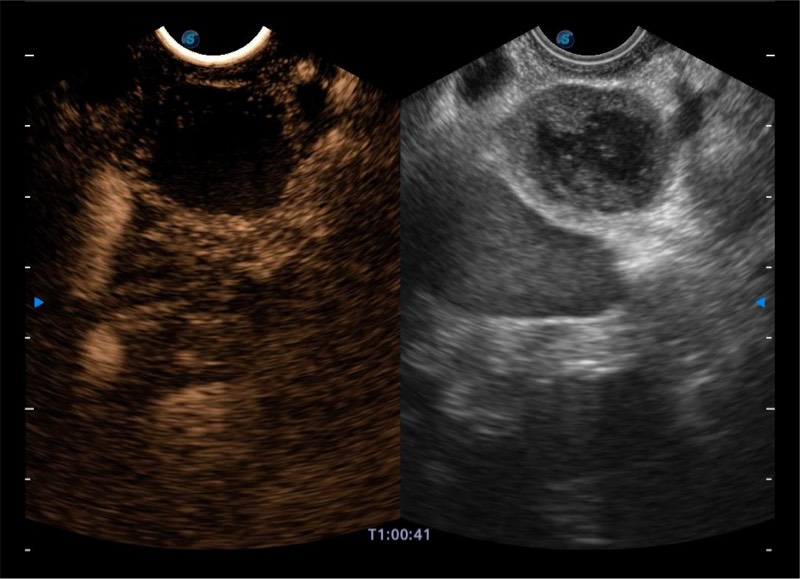

基于二十年的超声技术积累,乐玩lewin国际提供了最新一代的独立超声主机,在提供高质量图像的同时满足多学科使用。具备常见多普勒技术并提供弹性成像、声学造影等高端影像技术。新一代传感器具有更强的抗干扰能力并减少图像伪影。

• 4-12MHZ宽频输出